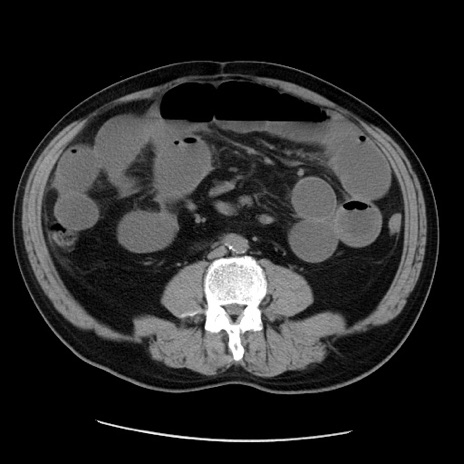

症例20(横断像)

【症例】 60歳代男性

【主訴】 腹部膨満、嘔吐

【現病歴】5日前頃より倦怠感を認め食事量減少し4日前の朝嘔吐、食事摂取困難となった。 3日前近医受診し点滴施行され整腸剤などを処方された。 当日他院を受診し、腹部膨満著明、炎症反応の上昇(CRP10.8、WBC11200)あり、紹介受診となる。

【身体所見】 意識JCS1 受け答えがはっきりしないBP 111/57mHg、 P 67bpm、、BT35.2°C、SpO2 97%(RA)、 腹部:膨隆、打診で鼓音あり、全体的に圧痛有り、腸蠕動音(-)、反跳痛ははっきりせず。

【データ】WBC 11400、CRP 14.20